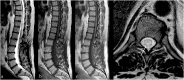

Background: Vascular lesions of the spinal cord are rare but potentially devastating conditions whose accurate recognition critically determines the clinical outcome. Several conditions lead to myelopathy due to either arterial ischemia, venous congestion or bleeding within the cord. The clinical presentation varies, according with the different aetiology and mechanism of damage.

Purpose: The aim is to provide a comprehensive review on the radiological features of the most common vascular myelopathies, passing through the knowledge of the vascular spinal anatomy and the clinical aspects of the different aetiologies, which is crucial to promptly address the diagnosis and the radiological assessment.